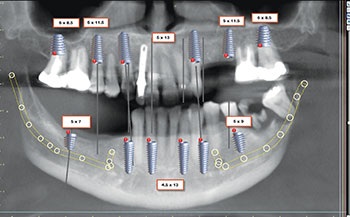

Surgery was uneventful. Extractions, site preparations and implant placements went according to plan (Fig. 3). In the maxilla, we placed six implants following the “All-on-6” concept, ensuring posterior spread for optimal load distribution. Six implants were also placed in the mandible following a similar approach.

All implants achieved excellent primary stability (>35 Ncm Torque and ISQ values averaging 72 to75), which allowed us to proceed with immediate loading (Fig. 4). Using SprintRay 3D printed provisionals in OnX Tough 2 resin, we delivered fixed temporaries the next day post-surgery (Figs. 5–8).

Just as we were about to finalize her case—taking definitive scans for zirconia full arches utilizing direct to MUA Vortex screws (Fig. 10) to be milled by LA Dental Implant Lab (Fig. 11)—the unexpected happened. Implant site #3 (maxillary right first molar) was mobile, causing discomfort to the patient during functional testing.

A surgical approach was planned for the atraumatic removal of the failed implant. We placed a Noris Medical pterygoid implant anchored in the medial pterygoid plate, achieving excellent primary stability (50 Ncm torque). The pterygoid implant allowed us to regain distal maxillary support without sinus augmentation or zygomatic implants.

To adapt the restoration to the new implant position, we used the iMetric digital verification system, capturing scans of the maxillary arch with the new pterygoid implant. A new set of provisional restorations was fabricated in-house using SprintRay OnX Tough 2 resin and immediately loaded the next day again with a screw-retained Vortex (Fig. 12).